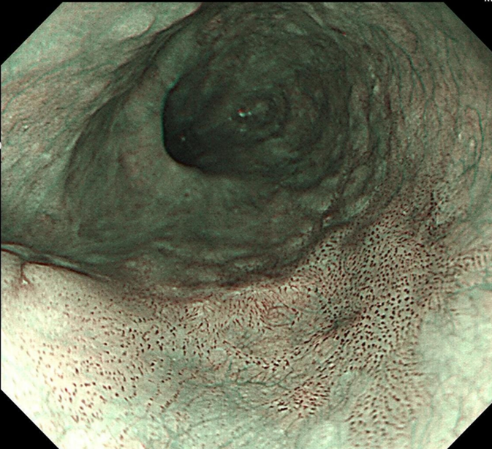

通过两个案例,一起直观地感受一下特殊内镜检查与普通胃肠镜有何差别

【早期食管癌】

【早期胃癌】